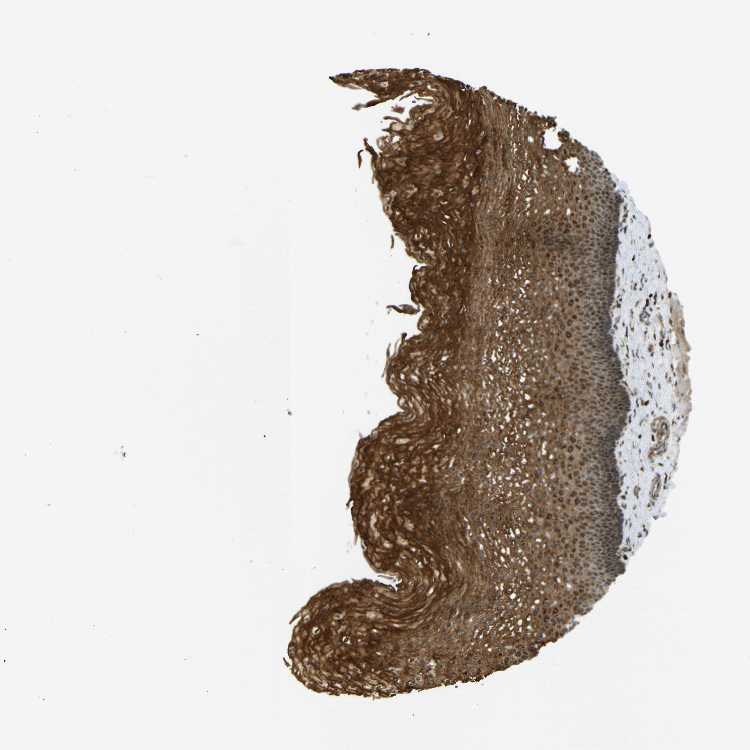

ESOPHAGUS - Antibody stainingi

Antibody staining in the annotated cell types in the current human tissue is reported as not detected, low, medium, or high, based on conventional immunohistochemistry profiling in selected tissues. This score is based on the combination of the staining intensity and fraction of stained cells.

Each image is clickable and will lead to virtual microscopy that enables deeper exploration of all samples and also displays staining intensity scores, fraction scores and subcellular localization as well as patient and tissue information for each sample.

Antibody HPA014030

Squamous epithelial cells High